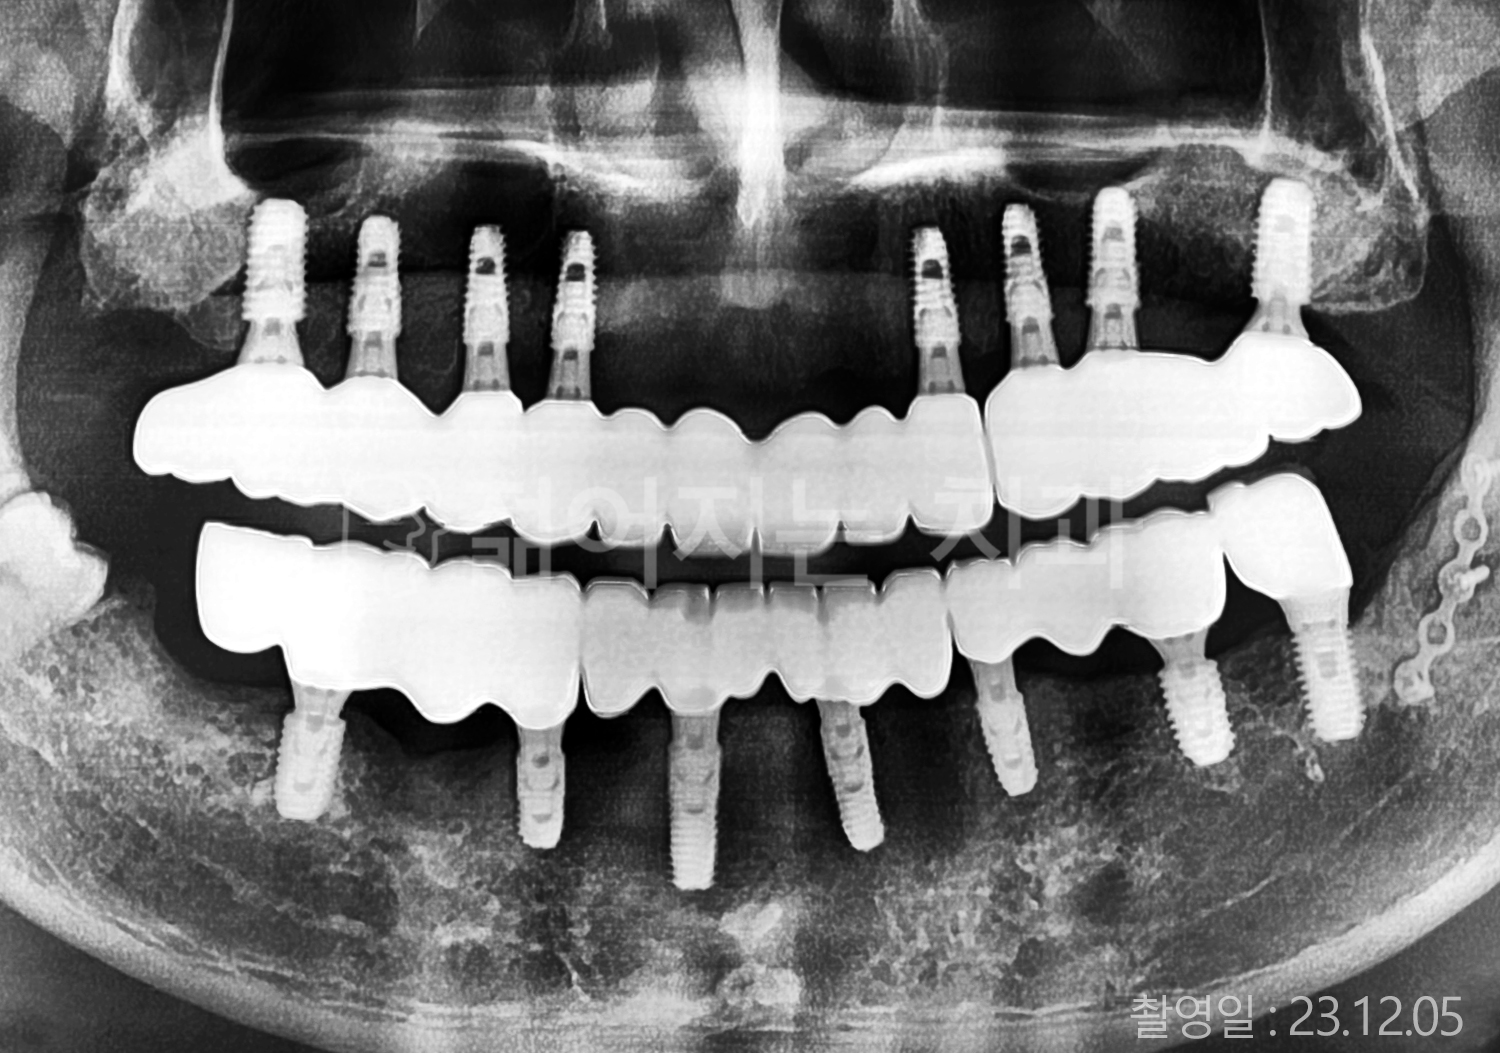

• 50대 고혈압, 당뇨, 고지혈증 전체치아 10개 이상 임플란트

• 60대 골다골증, 간경화 전체치아 10개 이상 임플란트

• 60대 고혈압, 고지혈증 전체치아 10개 이상 임플란트

• 50대 고혈압, 당뇨 전체치아 10개 이상 임플란트

• 60대 고혈압 전체치아 10개 이상 임플란트

• 60대 전체치아 10개 이상 임플란트

• 60대 고지혈증 전체치아 10개 이상 임플란트

• 40대 전체치아 10개 이상 임플란트

• 70대 전체치아 10개 이상 임플란트